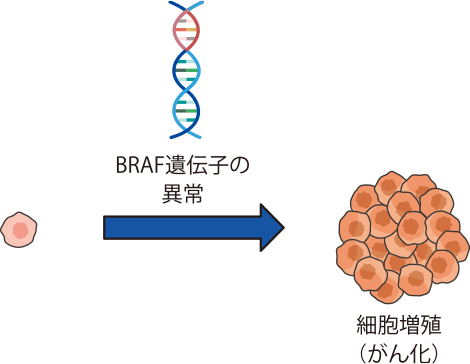

BRAF遺伝子変異は、細胞増殖を促す信号の通り道であるRAS/BRAF/MEK/ERK経路の途中にあるBRAFという分子の遺伝子が変異したものです。特にV600E変異が非小細胞肺がんの発生と増殖に関係しています。BRAFV600変異は、非小細胞肺がんの約1~3%に認められます。

BRAF遺伝子検査とは

細胞を増やすときに重要な働きをするBRAFというタンパク質があります。

そのタンパク質を作るBRAF遺伝子に変異(異常)が起こると、無秩序に細胞が増え続けて(増殖)、がん細胞が大きくなります。

BRAF遺伝子の変異は、悪性黒色腫などでは多い(約40%に発現)ことが知られていますが、非小細胞肺がんでは1~3%と少ないと推計されます。

また、肺がんのBRAF遺伝子の変異のタイプとしては、BRAFタンパク質を構成しているアミノ酸の600番目であるバリン(V)が、グルタミン酸(E)に変わった(V600Eと記されます)ものが最も頻度が高く約半数、他の変異(non-V600E変異)が半数と考えられています。